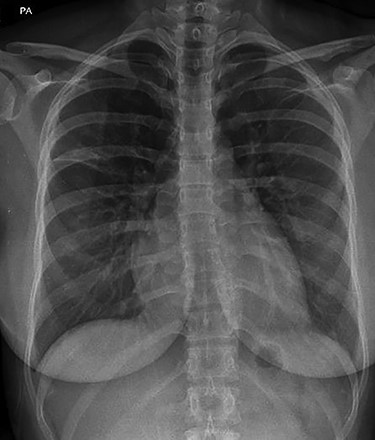

The case was rediscussed at the lung multidisciplinary meeting, and the plan was for the patient to undergo thoracic surgical intervention to remove the mass due to its uncertain nature. As the patient had remained asymptomatic with no haemoptysis and there was no interval change in the mass on surveillance imaging, the patient was brought back for follow-up bronchoscopy. This demonstrated evidence of a previous inflammatory process with cavitation and destruction of sub-lobar bronchial tree. Impression was that the last bronchoscopy had cleared the airway and the patient coughed and cleared the lung distally. The procedure was largely uncomplicated. The patient was subsequently discharged after they had recovered from the anaesthetic. Serial chest radiographs demonstrated almost complete resolution of the right upper lobe mass (Fig. 4). Furthermore, serial IgE titres demonstrated decreasing levels, and this was without the patient being commenced on any antifungal treatment.

Plain chest radiograph demonstrating resolution of the right upper zone mass.